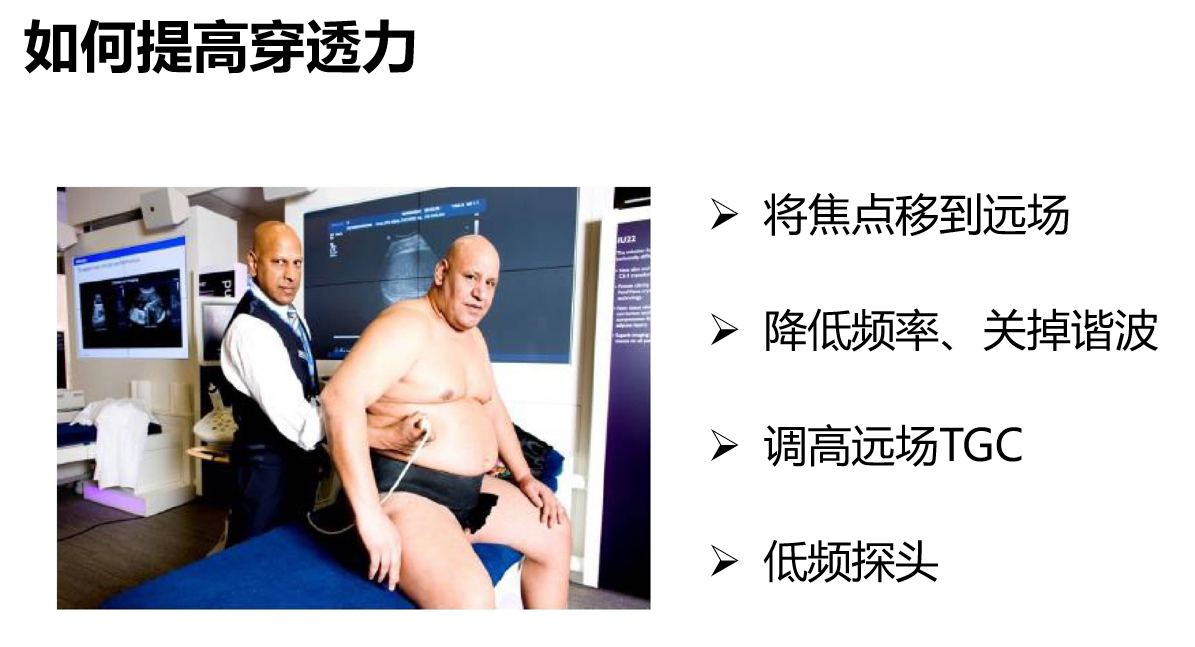

如何提高穿透力:

像图中这个肥胖患者,如何提高穿透力?

将焦点移到远场;降低频率、关掉谐波;调高远场TGC;更换频率更低的探头,这些调节都可以提高穿透力。